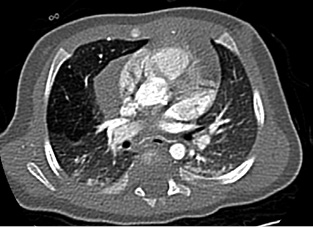

Gestante de 44 años a la que, en el control ecográfico del segundo trimestre, detectan una masa quística pulmonar de 21 x 19 x 17 mm, sin otras malformaciones asociadas. Cribado de cromosomopatías negativo y resto del embarazo sin incidencias, salvo hipotiroidismo subclínico. En controles subsiguientes persiste la masa con leve disminución de su tamaño sin asociar otros hallazgos patológicos. Nace un varón a término con llanto espontáneo, adecuado tono y coloración, con exploración física a las 8 horas de vida sin alteraciones. Ante hallazgos en ecografía prenatal, se solicita una radiografía de tórax que evidencia un aumento de densidad de morfología nodular, de unos 2 cm de diámetro, localizado en campos medios-inferiores derechos, que presenta imágenes radiolucentes milimétricas en su interior (Fig. 6). Es dado de alta sin incidencias a las 48 horas de vida. Figura 6. Radiografía del paciente en el primer día de vida. Se valora de forma presencial en consulta de neumología al mes de vida. El paciente no ha presentado infecciones respiratorias ni episodios de cianosis. Realiza tomas de manera correcta. Adecuado desarrollo ponderoestatural. Patrón respiratorio con rachas de polipnea sin tiraje. Para filiar mejor la lesión, se solicita TACAR, que se realiza a los 2 meses de vida, en el que se observa hipoatenuación e hipovascularización en lóbulo medio sin lesiones quísticas definidas. No efecto masa sobre estructuras mediastínicas ni parénquima pulmonar adyacente. Hallazgos compatibles con enfisema lobar (Fig. 7). Figura 7. TACAR del paciente a los 2 meses de vida. Controles trimestrales durante el primer año de vida. El paciente permanece asintomático. Se deriva a cardiología para descartar cardiopatía estructural asociada. A los 9 meses, radiografía de control que muestra disminución del área hiperdensa respecto al estudio previo.